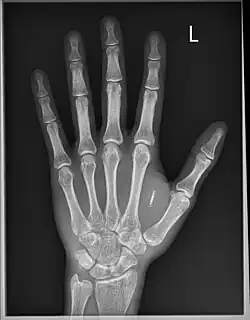

Le , le scientifique Britannique Mark Gasson s'est fait implanter chirurgicalement un dispositif RFID avancé au sein d'une capsule de verre dans la main gauche. En , l'équipe de Mark Gasson démontra comment un virus informatique pourrait infecter sans contact son implant et ensuite être transmis à d'autres systèmes[3]. Mark Gasson établit donc qu'en implémentant de la technologie, la séparation entre l'homme et la machine devient alors théorique, celle-ci étant alors perçue par l'organisme comme faisant partie intégrante du corps. En raison de cette évolution dans notre compréhension de ce qui constitue notre corps et ses limites, il est alors crédité comme étant le premier homme infecté par un virus informatique. Il n'a pas l'intention de retirer son implant[4].

Mikey Sklar se fait implanter une puce dans la main gauche et filme la procédure[6].